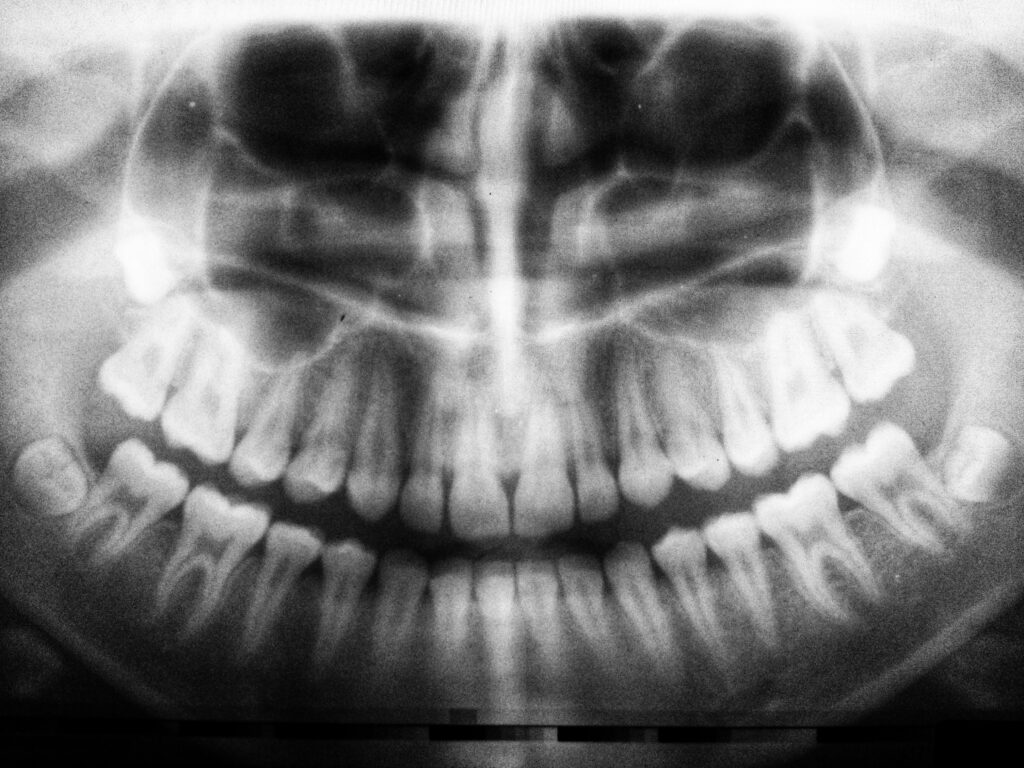

Discover the factors behind wisdom teeth impaction, including diet and facial growth, and learn more in Glendale, AZ.

Why Wisdom Teeth Are So Often Impacted Read More »